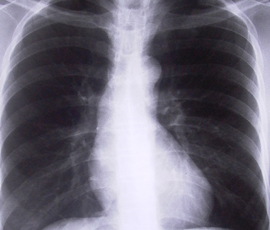

TB is an infection caused by the TB bacterium Mycobacterium tuberculosis. It commonly affects the lungs. While it grew rare in the UK due to BCG (TB) vaccination, improvements in living standards and the introduction of effective antibiotic treatment, it has been on the increase since the late 1980s. TB also remains a major global health problem with nearly nine million new cases and 1.4million deaths in 2011.